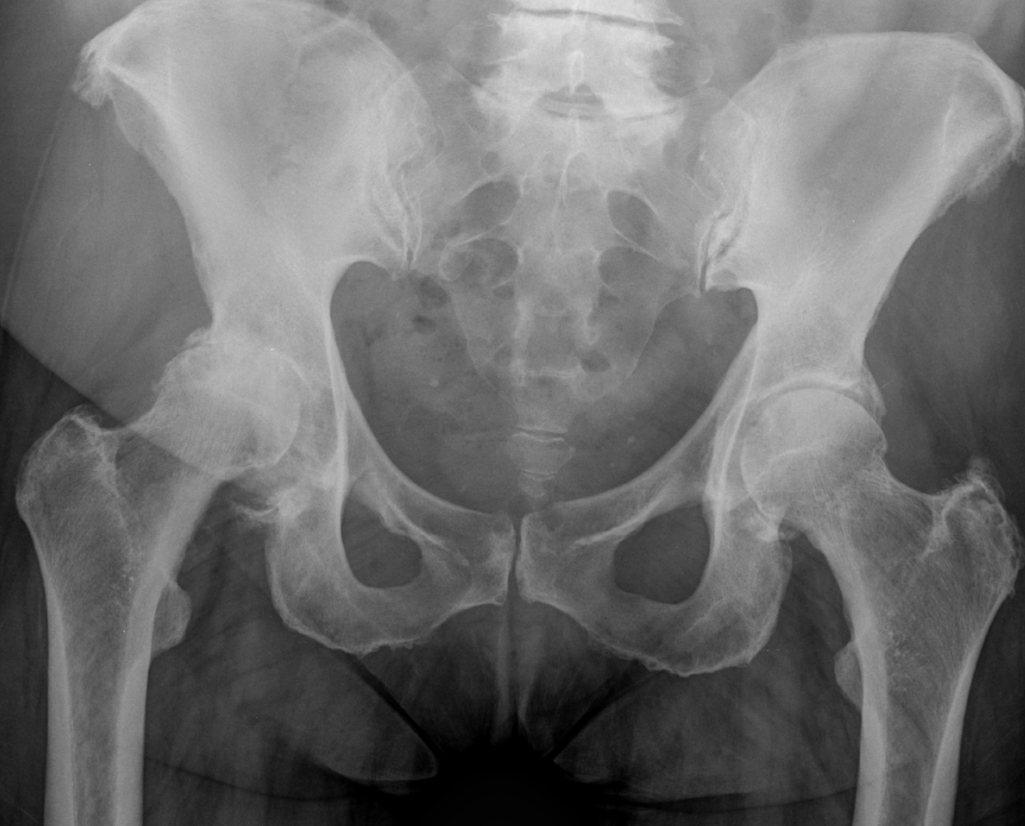

3. Avascular Necrosis right femoral head